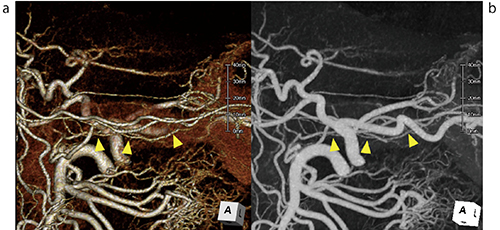

図2 膵十二指腸動脈のアーケード(pancreaticoduodenal arcade)の描出(▲)

a:VR画像、b:MIP画像